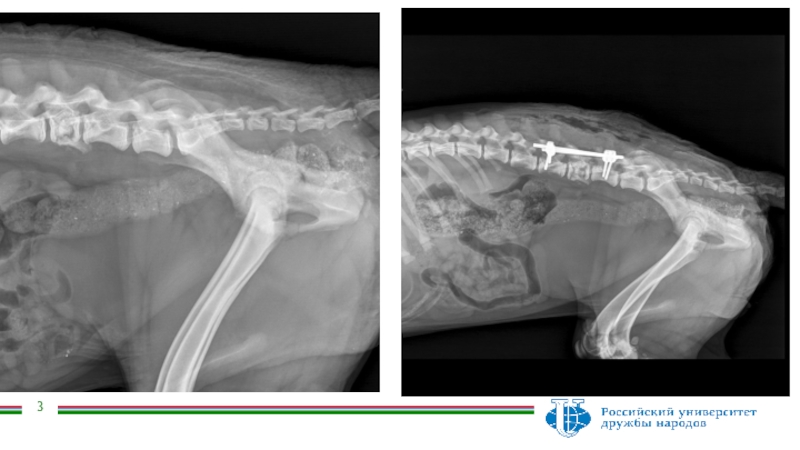

Анамнез Собака – метис по клички Борис, 8 месяцев, кобель.08.2018 была автотравма,по результатам обследования диагностировали компрессионный перелом позвоночника на уровне L5. Степень неврологического дефицита-4. Была проведена стабилизация позвоночного столба.

Собака – метис по клички Борис, 8 месяцев, кобель.

08.2018

была автотравма,по результатам обследования диагностировали компрессионный перелом позвоночника на уровне

L5. Степень неврологического дефицита-4.

Была проведена стабилизация позвоночного столба.